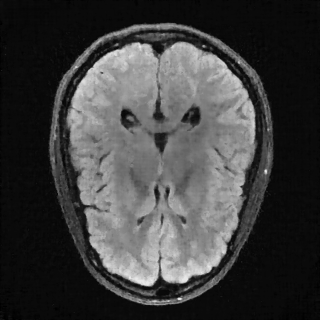

This article presents a novel undersampled magnetic resonance imaging (MRI) technique that leverages the concept of Neural Radiance Field (NeRF). With radial undersampling, the corresponding imaging problem can be reformulated into an image modeling task from sparse-view rendered data; therefore, a high dimensional MR image is obtainable from undersampled $k$-space data by taking advantage of implicit neural representation. A multi-layer perceptron, which is designed to output an image intensity from a spatial coordinate, learns the MR physics-driven rendering relation between given measurement data and desired image. Effective undersampling strategies for high-quality neural representation are investigated. The proposed method serves two benefits: (i) The learning is based fully on single undersampled $k$-space data, not a bunch of measured data and target image sets. It can be used potentially for diagnostic MR imaging, such as fetal MRI, where data acquisition is relatively rare or limited against diversity of clinical images while undersampled reconstruction is highly demanded. (ii) A reconstructed MR image is a scan-specific representation highly adaptive to the given $k$-space measurement. Numerous experiments validate the feasibility and capability of the proposed approach.